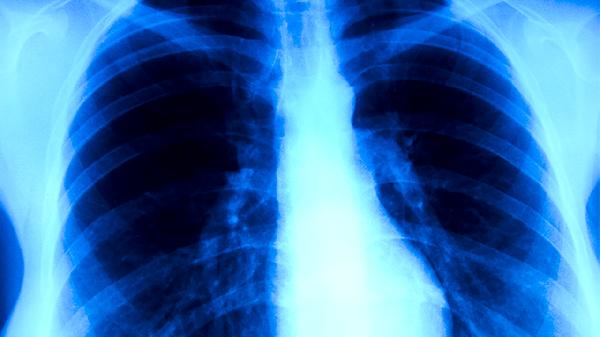

治疗肺炎可使用的中药主要有麻黄、杏仁、石膏、甘草、鱼腥草等。肺炎多由外感风热、痰热壅肺等因素引起,中药治疗需辨证施治,建议在中医师指导下使用。